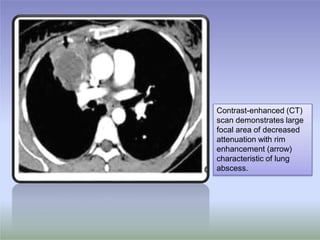

Contrast-enhanced (CT)

scan demonstrates large

focal area of decreased

attenuation with rim

enhancement (arrow)

characteristic of lung

abscess.

Contrast-enhanced (CT) scan demonstrateslarge focal area of decreased attenuation with rim enhancement (arrow) characteristic of lung abscess.